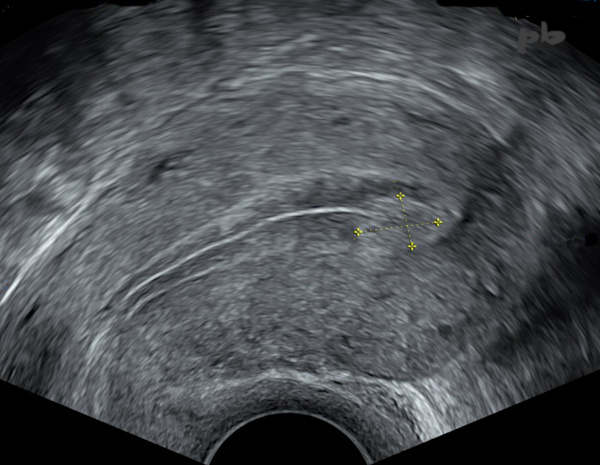

2 – Résidus trophoblastiques

(même patiente que 1)

Fausse couche. 4 semaines plus tard.

Il ne persiste qu’un fragment hyperéchogène (entre les croix), bien limité : résolution spontanée en cours.